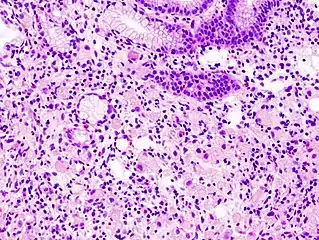

A signet ring-like foamy macrophage, which may mimic a cancer cell, but the texture of the nucleus is similar to that of a normal macrophage.

The name of the cell comes from its appearance; signet ring cells resemble signet rings. They contain a large amount of mucin, which pushes the nucleus to the cell periphery. The pool of mucin in a signet ring cell mimics the appearance of a finger hole and the nucleus mimics the appearance of the face of the ring in profile.